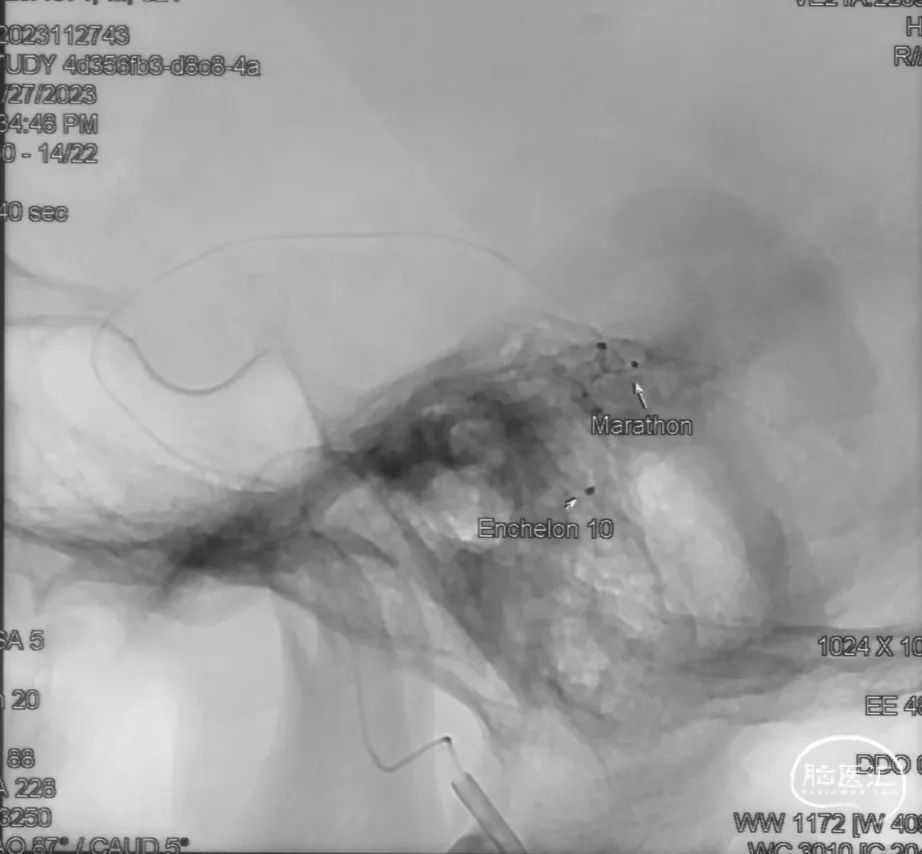

经Marathon微导管手推造影明确微导管位于瘘口动脉端,Echelon-10微导管位于瘘口引流静脉起始端处扩张的静脉球内。

由于瘘口流量大,为了防止栓塞材料过度弥散,并逃逸至深静脉,首先通过Echelon-10微导管向静脉球内填入Feng 12/40、Feng 10/30两枚弹簧圈,限制后续液态栓塞材料仅在静脉起始部弥散。

随后回撤Echelon-10微导管,并通过Echelon-10微导管和Marathon微导管交替注入Onyx-34、Onyx-18,此时可见Onyx首先被血流冲至静脉球内,但被弹簧圈篮筐限制,并在瘘口范围内弥散。

通过“注射-停顿-再注射”,Onyx进一步在瘘口及供血动脉段和引流静脉起始部弥散满意

Onyx胶铸型显示瘘口形态。